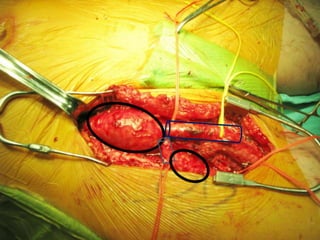

Que nous apprennentces cas Anévrysmes fémorale profonde?  Épidémiologie  Présentation clinique  Indication opératoire  Reconstruction chirurgicale Autres anévrysmes ? Se méfier de Rupture ! 1ère manifestation …une complication Ligaturer ! Approche

72 59 ATCD: PABI’99 re: AIliaquebil ATCD: Db , ROH Korsakoff, MCASPAC, fempop bilat Anévr popl. Suivi Anévr fém et popl RC: référé rupture…en fait «non» mais symptomatique Quest: … Quest.:C.I. non limitante E.P.: masse puls. > 5cm ing. D non doul et autres… E.P.: masse pulsatile >5 cm ing G doul palpation, nécrose sèche extr dist un orteil non doul Pls périph N Doppler Angioscan: dimensions anévr. ? Angioscan: dimensions Anévr ?

Cas #1 72ans Cas #2 59 ans  Suivi  ATCD  PABI  Particularités  Anévrysme Fémorale profonde  Cutler-Darling type 1  Symptomatique  ATCD  Fem-pop. Bilatéraux…  Particularités  Korsakoff  Cutler-Darling type 2 thrombosés